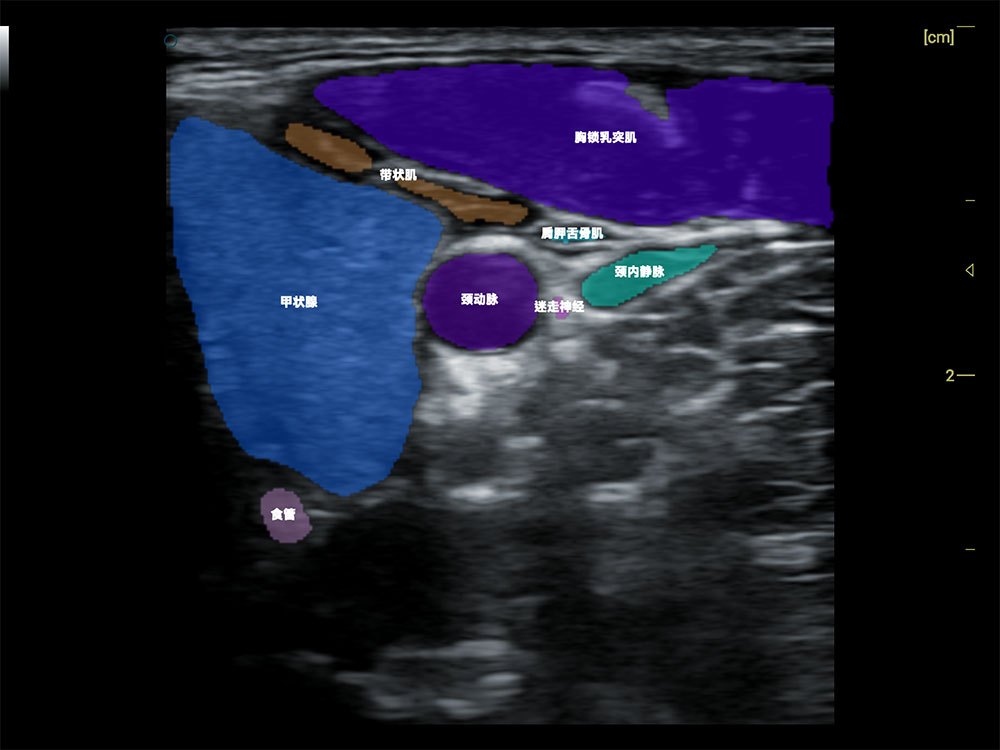

• AI 智能识别甲状腺病灶

• AI 辅助诊断,提速降错